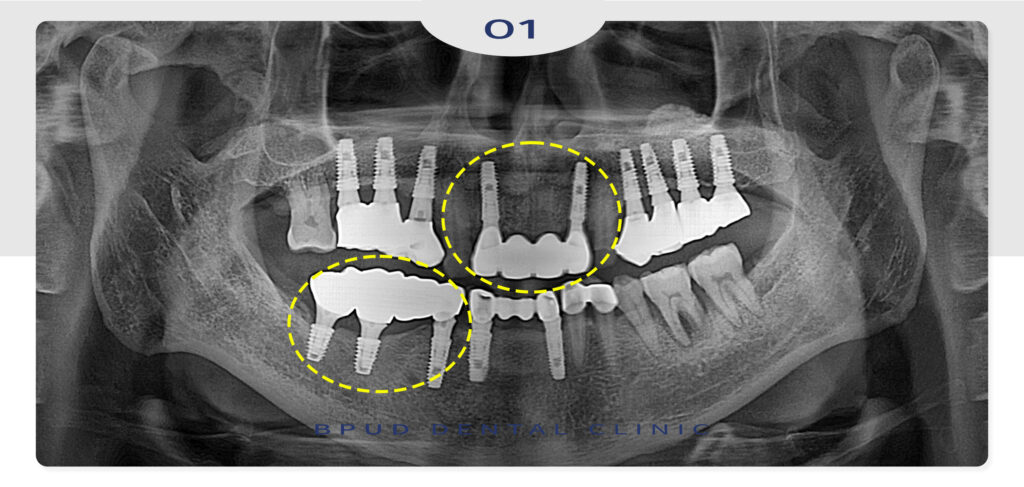

23.05.16

먼저 파절된 앞니 보철을 제거하고

임플란트를 마무리 하였고,

오른쪽 아래 어금니 부위 임플란트도

신속히 제거를 우선적으로 진행하였습니다.

발치 후 뼈이식을 동시에 진행하여

본래의 뼈와 충분히 단단하게 융합될 수 있는

기간을 기다려 준 뒤, 식립을 진행하기로 하였는데요.

재수술이 필요한 상황에서는 기존 임플란트를 제거하고

주변 조직 상태를 면밀히 파악하는 것이 우선으로

뼈가 충분히 남아 있는 경우라면 식립 각도나

보철 설계를 조정해 재식립이 가능하지만

뼈흡수가 진행된 상태라면 골이식을 병행하거나

회복 기간을 확보한 후 치료를 진행해야 합니다.

위쪽의 경우 상악동 거상술이 필요할 수 있으며

잇몸이 위축된 부위라면 연조직의 이식도

고려해 보아야 합니다.